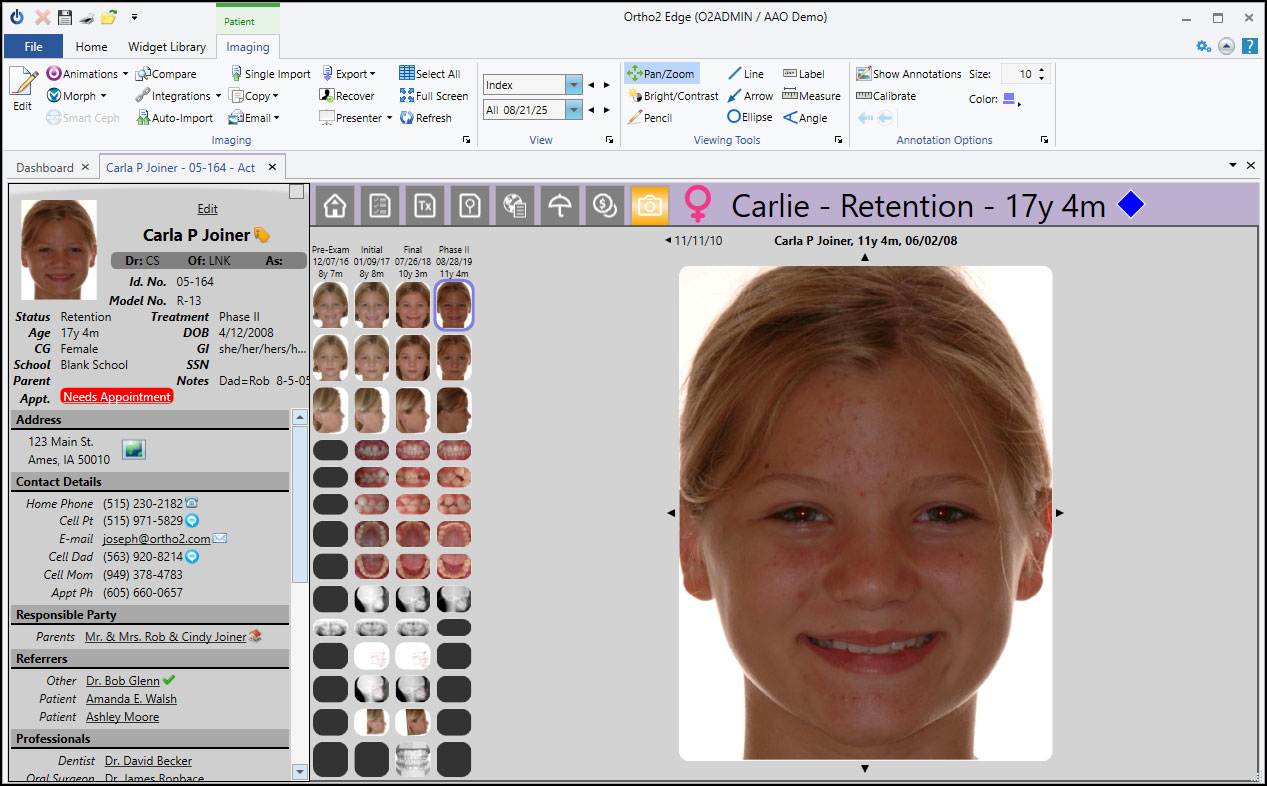

Quick and easy photo imports are just the start of the streamlined process for Edge Imaging. Images appear throughout the program so you can quickly identify patients, view photos in the Treatment Hub, and quickly email images to other professionals.

Fix photos with clear editing, and unlimited undos allows you to revert to the original image. Setup comparisons to view images from separate timepoints and show your patients the difference treatment has made. From importing images to timepoint comparisons, organizing and compiling photos, Edge Imaging does it all.

Edge Imaging is one of the most versatile imaging solutions out there. On top of your patient images, you can add any non-image file, including STL files, to the cloud for safe storage. Use it on any workstation with no additional costs and no dongles required.